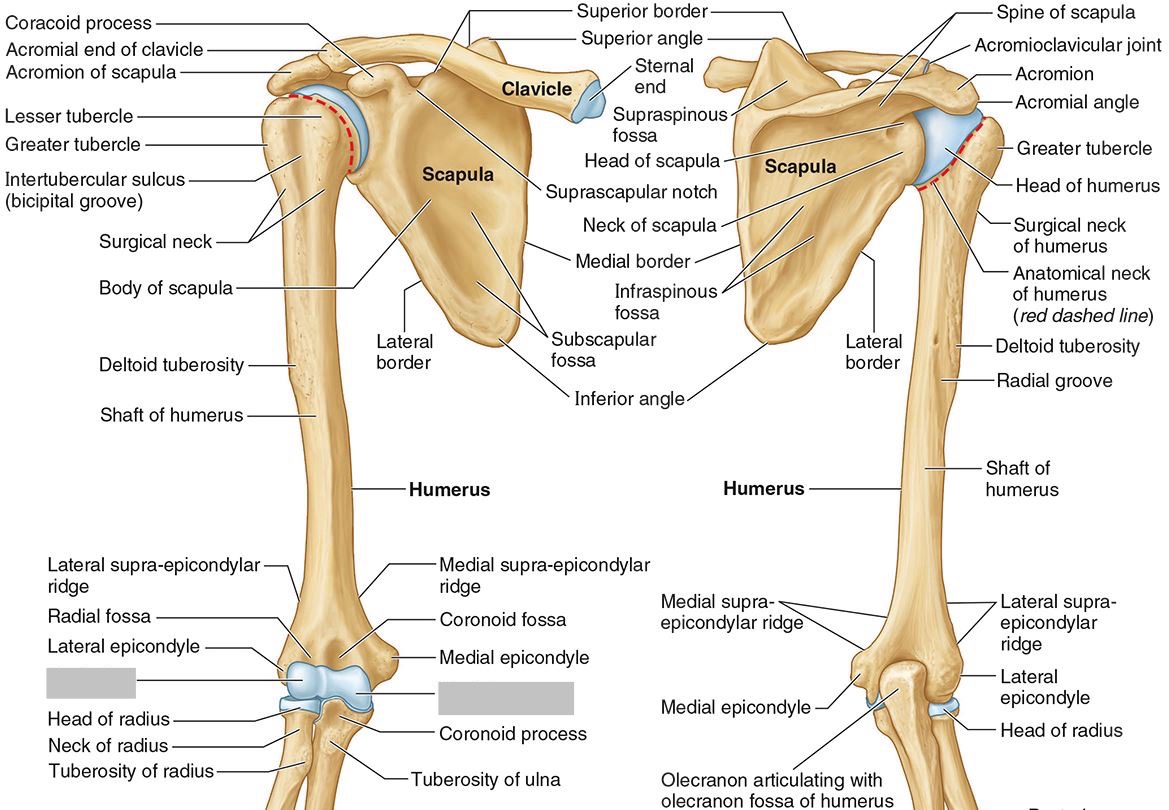

What part of the humerus is this?

The head of the humerus articulates with the scapula at the glenohumeral joint.

What part of the humerus is this?

The anatomic neck is an indentation distal to the head and provides an attachment for the fibrous joint capsule of the glenohumeral joint.

What part of the humerus is this?

The greater tubercle lies lateral and distal to the anatomic neck.

What part of the humerus is this?

The lesser tubercle lies on the anterior/medial side of the humerus, just distal the anatomic neck.

What part of the humerus is this?

The intertubercular (bicipital) groove lies between the greater and lesser tubercles.

What part of the humerus is this?

The surgical neck is a narrow area distal to the tubercles. It is a common site for proximal humerus fractures.

What part of the humerus is this?

The humeral shaft features the deltoid tuberosity laterally for the distal insertion of the deltoid muscle.

What part of the humerus is this?

The radial groove is an oblique depression that contains the radial nerve and deep brachial artery.

Which parts of the humerus is this?

The medial and lateral epicondyles are distal prominences to which many forearm tendons attach, near the elbow joint.

Which parts of the humerus is this?

The medial and lateral supracondylar ridges extend superiorly from the medial and lateral epicondyles.

Which parts of the humerus is this?

The trochlea and the capitulum (the condyles) are the most distal surfaces of the humerus, where it articulates with the forearm bones at the elbow joint

What part of the humerus is this?

The olecranon fossa is a posterior depression above the trochlea that receives that olecranon process of the ulna

What part of the humerus is this?

The coronoid fossa is an anterior depression above the trochlea that receives that coronoid process of the ulna.